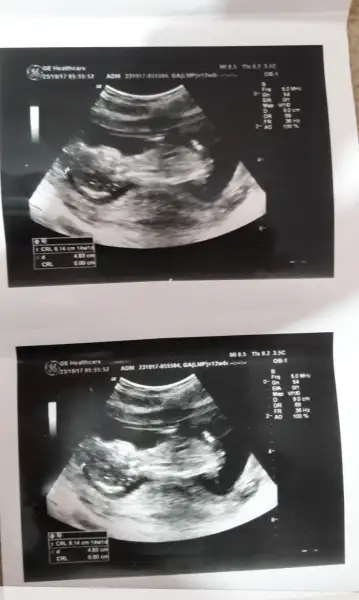

Cinsiyeti bilmem de senin ki düzgün çocuğa benziyor benim ki uzaylı gibi bende anlamadımkizlar bu bizim ultrasyon sonunda yaptim bana bi cinsiyet yorumu yapin ya 2 haftadaha bekoicem zaten yanliz kesem cok garip geliyor bana

Cinsiyeti bilmem de senin ki düzgün çocuğa benziyor benim ki uzaylı gibi bende anlamadım

Haftamız aynı ama ben bişey anlamadım bu durumdan:))benimki 10 haftadayken uzayli gibiydi acayip bicimsizdi. simdi benimkide bana ortadan kesem sıkıyor gibi geldi. sen kac haftaliksin ben kollarini goremedim benimmi bi yan bi arka